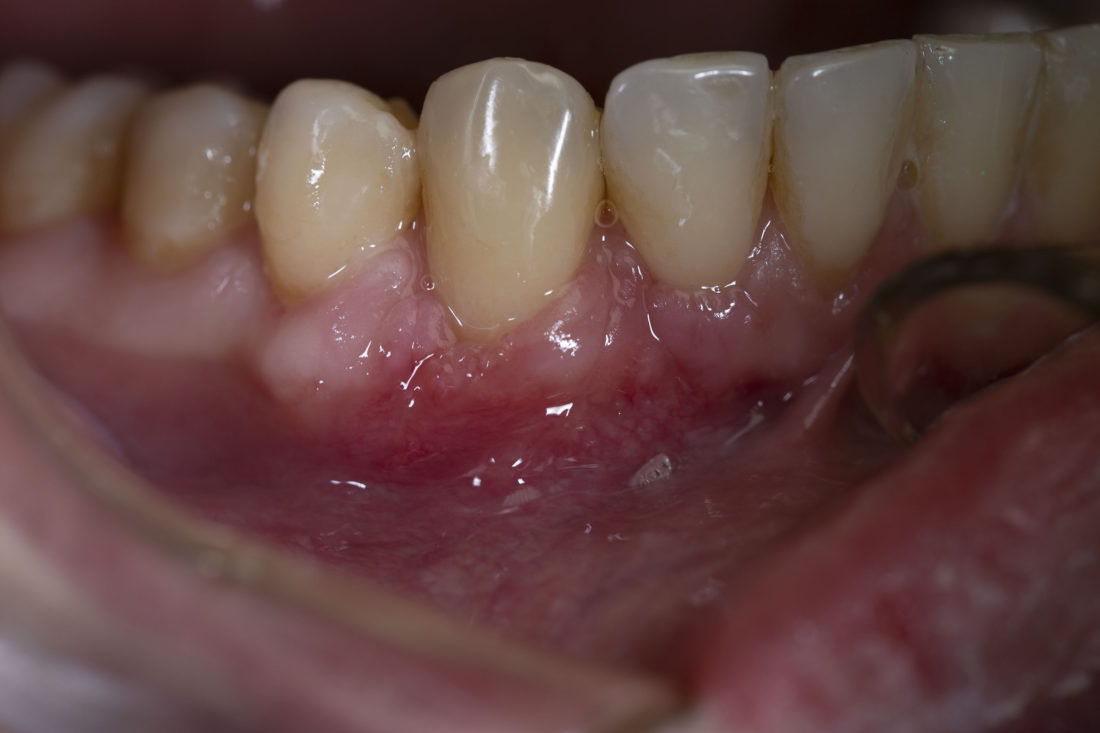

Результати наших робіт

• гінгівіт (запалення ясен) та пародонтит (запалення тканин під ними, зазвичай розвивається як ускладнення гінгівіту), типові ознаки запального процесу – набряк та кровоточивість м’яких тканин;

• опущення ясен – поступова втрата, атрофія тканини. Рецесія ясен 3-4 ступеня супроводжується втратою міжзубної, кісткової тканини.

• видиме опущення ясен та оголення зубних коренів, часто – прикореневий карієс.